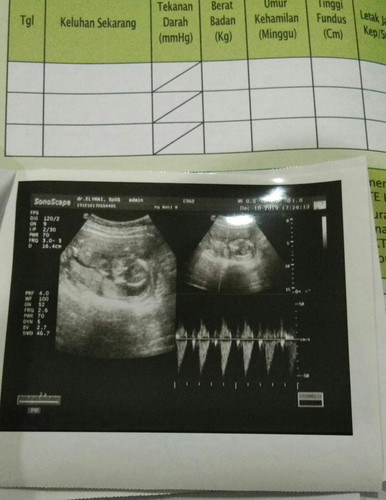

Assalamualaikum bunda.. Selamat malam.. Minta sarannya dong bun.. ??..saya barusan USG alhamdulillah janinnya sehat normal ketubannya bagus ddj nya bagus sehat.. Tapi yg jadi masalahnya dokter bilang berat badan saya yg kurang skrg usia kehamilan saya 16w5d dari pertama hamil baru naik 1 1/2 kg.. Dokter bilang seharusnya naiknya sudah 4kg an gitu.. ?..pdhal saya juga udah berusaha makan makanan apapun itu karna nafsu makan juga udah enak alhamdulillah.. Tapi masih naiknya sedikit.. Ada nggak bunda bunda disini yg bb nya naiknya juga masih belum banyak.. Dan mohon sarannya.. Apa yg harus saya komsumsi agar cepat nambah bb ya bun.. Terimakasih bunda yg sudah mau jawab... Semoga selalu diberi kesehatan untuk pribadi dan keluarga.. Aamiin.. ??